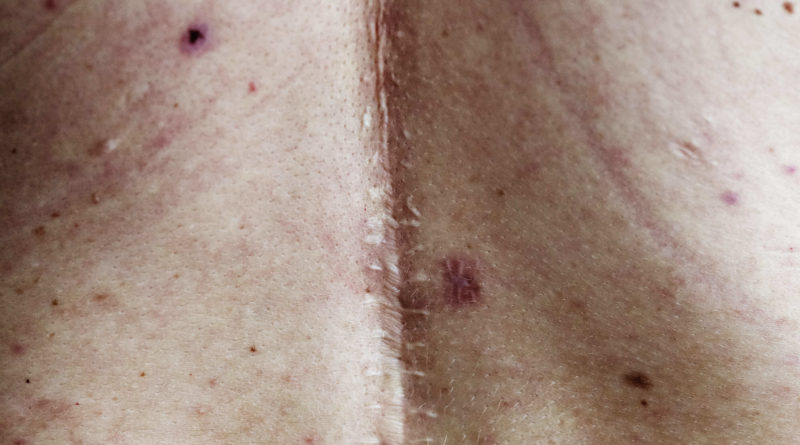

As marcas no corpo deixadas por cicatrizes podem trazer lembranças das mais diferentes formas, quase sempre dolorosas, sendo os procedimentos cirúrgicos, como mastopexia, cirurgia de prótese de silicone, abdominoplastia e lipoaspiração alguns exemplos. Outras vezes, cirurgias emergenciais, não programadas e realizadas de forma imprevista, também são motivadoras destas “lembranças” estampadas na pele.

De forma técnica, é possível explicar que uma cicatriz é formada por um tecido fibroso que substitui a pele danificada e pode apresentar uma aparência diferente da pele ao redor, podendo ser mais escura, mais clara, mais espessa, mais fina ou mais brilhante. Mas, ao contrário do que muitos pensam, elas não são, necessariamente, “definitivas”: atualmente, existem tratamentos clínicos e estéticos que podem amenizar a aparência dessas marcas, ou até mesmo removê-las por completo.

Para Giancarlo Pincelli, biomédico esteta e sócio da Hell Tattoo, clínica estética especializada em remoção de tatuagem e despigmentação de micropigmentação, o tratamento se difere para cada caso. “Quando, por exemplo, há a existência de tecido queloidiano, utilizamos lasers ablativos que fazem o recapeamento da superfície da pele”, diz o profissional, ressaltando que este “recapeamento” é associado a cremes específicos e até mesmo a pequenas injeções no local com fármacos que irão dar mais qualidade ao tecido, “impedindo que a cicatriz sofra expansão ou que o tecido fibrótico aproveite a região novamente”.

Pincelli explica que alguns casos são menos complexos, como a hiperpigmentação pós-inflamatória, que são aquelas manchas castanhas que ficam em torno da cicatriz e que dão a impressão dela ser maior do que realmente é. Com as tecnologias de laser, é possível resolver a situação em poucas sessões.